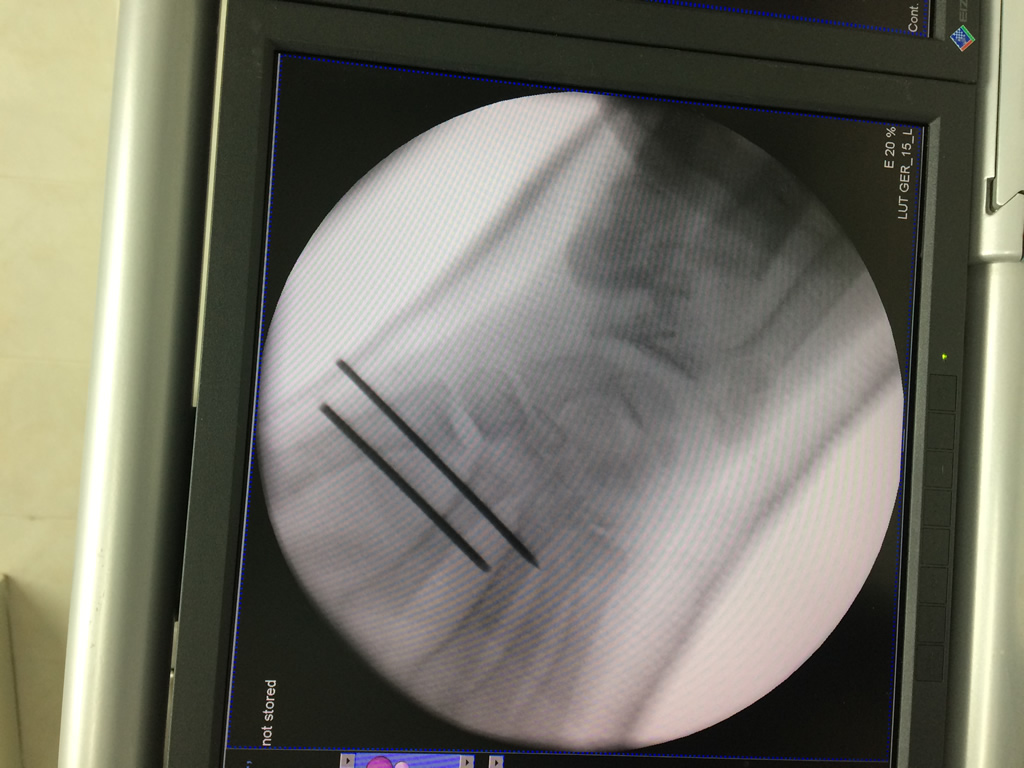

Calcaneo - Cirugías de Muñecas y Manos

Los procedimientos más comunes en cirugía de la mano son aquellos destinados a reparar traumatismos, incluyendo lesiones de tendones, nervios, vasos sanguíneos, y articulaciones; huesos fracturados; y quemaduras, cortes, y otros daños de la piel.